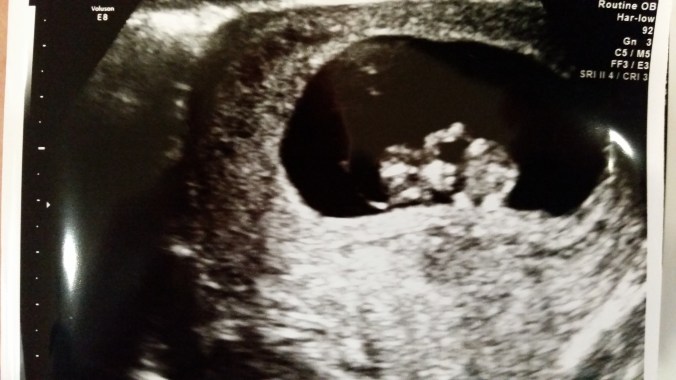

We graduated to the abdominal ultrasound in week 9. This was a HUGE milestone and one of the moments that really helped me relax and start getting more excited. I have serious anxiety with vaginal ultrasounds because I’ve had 10+ and all but my last 2 revealed bad news. Putting the ultrasound on my belly and seeing a baby inside made it so much more real and truly helped me relax and feel like things really were going well. We also heard the baby’s heartbeat with our home Doppler for the first time in week 9. 9w5d to be exact. Cinco de Mayo. Daniel didn’t want me to try because he knew it was a little early to be trying at home and knew I would FREAK out if I didn’t find it. Thankfully I found it pretty quickly. A nice, strong little heartbeat and it was so exciting!

Baby looking more like a baby! You can see little arm nubs. 9w2d measuring 9w3d. HR 174.